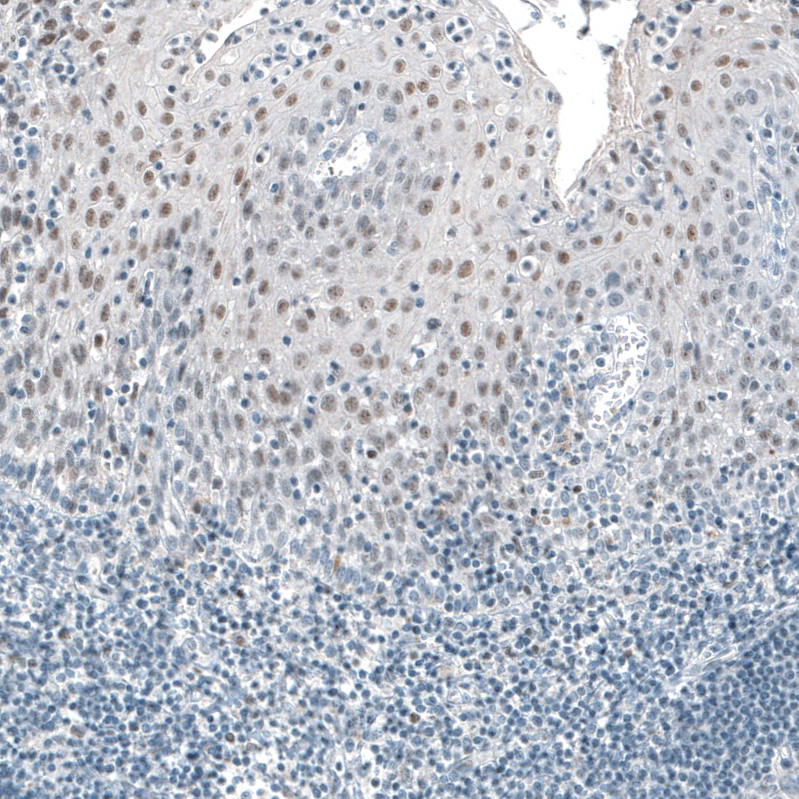

Immunohistochemistry analysis in human placenta and pancreas tissues using AMAb91439 antibody. Corresponding TET2 RNA-seq data are presented for the same tissues.